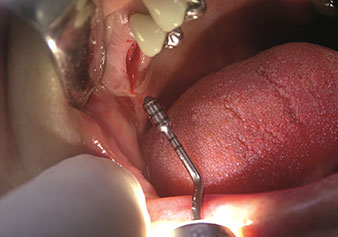

W&H also offers the perfect solution for the internal sinus lift.

Following preparation of the maxillary sinuses with the corresponding instrument set (Fig. 3), the new Z35P instrument (Fig. 4) is used to lift the membrane hydrodynamically. The same instrument set can also be used for piezosurgical preparation of the implant bed in increasing diameters (Figures 3 and 4 included with the kind permission of Dr Mario Kirste, Frankfurt/Oder).